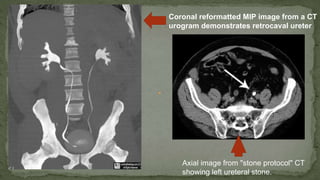

Coronal reformatted MIP image from a CT

urogram demonstrates retrocaval ureter

Axial image from "stone protocol" CT

showing left ureteral stone.